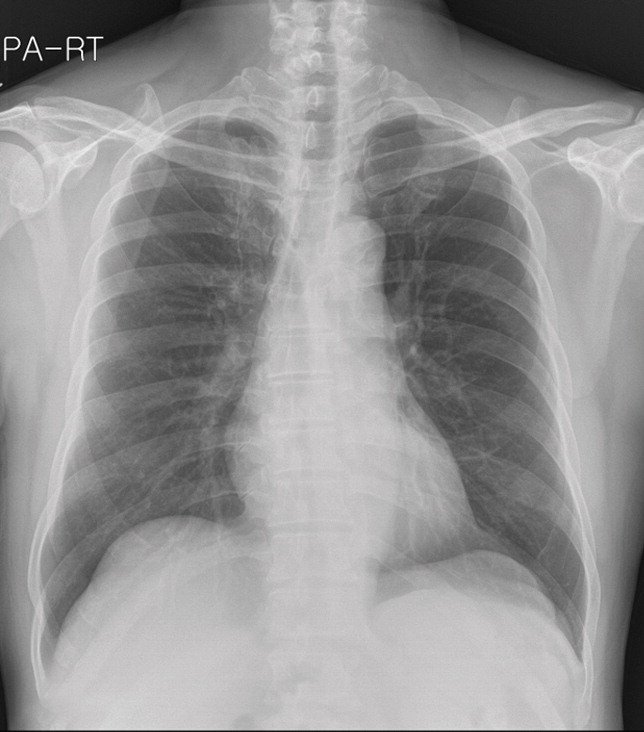

The images in the panels below highlight some of these difficulties. Example 1 shows the chest X-ray of a 62-year-old man with a tumor located in his upper right lung. The tumor is partially obscured by the collar bone and is difficult to see. When analyzed by a group of twelve radiologists, three members of the panel missed the tumor as part of their review. Though they recognized the presence of the tumor during a second review (more detail about that below).

Example 1: 62 year old man with adenocarcinoma